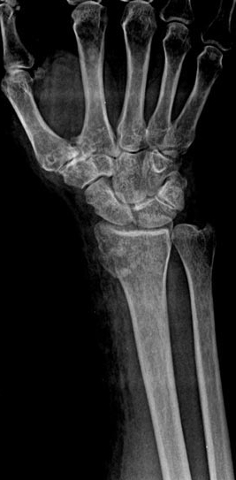

Fracture of Distal Radius